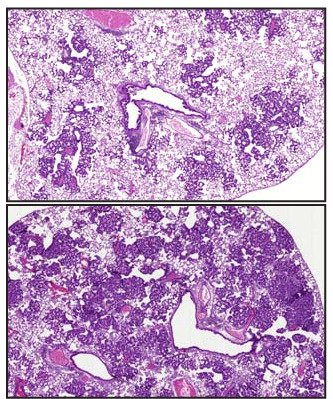

Healthy people and cancer patients alike use antioxidant supplements, including vitamins A, C, and E, as a daily cancer-fighting strategy despite lack of convincing scientific evidence. We discovered that dietary antioxidants actually accelerate lung cancer growth and metastasis. Antioxidants activate a protein called BACH1 which forces tumour cells to take up glucose and use it for aerobic glycolysis – i.e., the Warburg effect – which drives metastasis. Antioxidants produce similar effects in malignant melanoma and pancreatic cancer. The results suggest that cancer patients should avoid antioxidant supplements and that we may now design drugs that inhibit BACH1-induced glycolysis as a strategy to block metastasis.